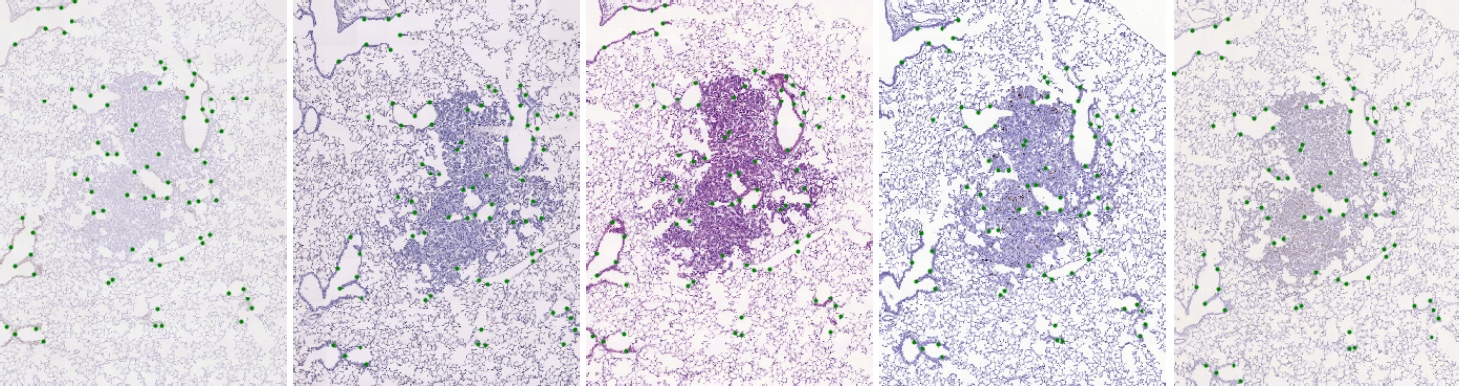

Lesion tissue - Unstained adjacent 3μm formalin-fixed paraffin-embedded sections were cut from the blocks and stained with Hematoxylin and Eosin (H&E) or by immunohistochemistry with a specific antibody for CD31, proSPC, CC10 or Ki67. Images of three mice lung lesions (adenoma or adenocarcinoma) were acquired with a Zeiss Axio Imager M1 microscope (Carl Zeiss, Jena, Germany) equipped with a dry Plan Apochromat objective (numerical aperture NA=0.95, magnification 40×, pixel size 0.174 μm/pixel).

Lung lobes - The images of the four whole mice lung lobes correspond to the same set of histological samples as the lesion tissue. They were also acquired with a Zeiss Axio Imager M1 microscope (Carl Zeiss, Jena, Germany) equipped with a dry EC Plan-Neofluar objective (NA=0.30, magnification 10×, pixel size 1.274 μm/pixel).

We have marked significant structures in the tissue with landmarks which are spread approximately uniformly over the tissue. Landmarks were manually identified in each image, with correspondences within each set, which allows us to validate the geometric registration accuracy between any two images in each set.